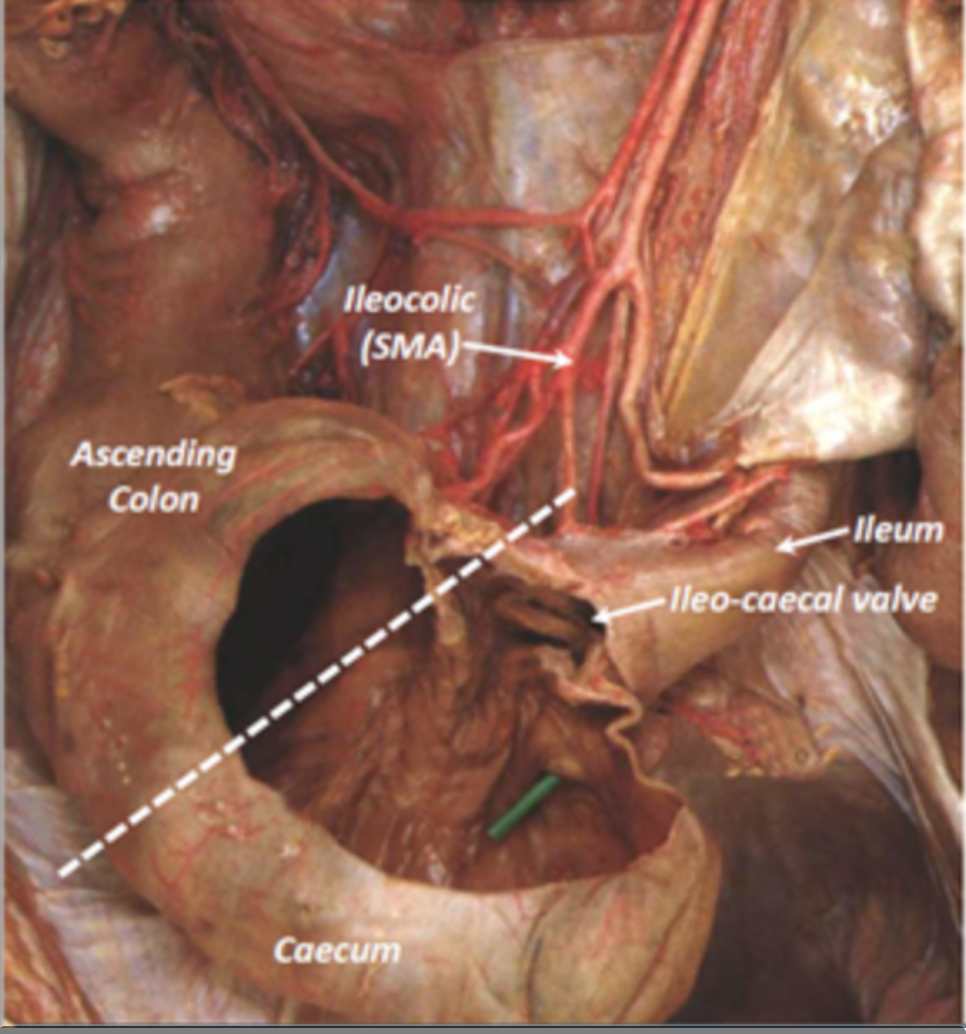

what vessel provides the caecum?

A

ileocolic artery –> branch of SMA

21

Q

What junction is found in the caecum?

What supplies the caecum?

Where does this artery come from?

Ileocaecal junction

Ileocolic artery which is a branch of the superior mesenteric artery